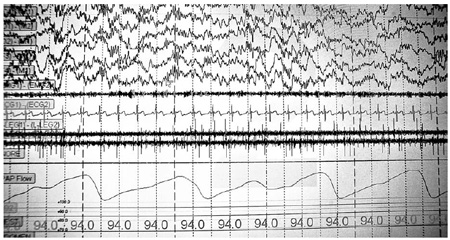

His clinic has four small bed- rooms. Before bed, the technicians place sensors on the patients to track sleep, breathing and movement.